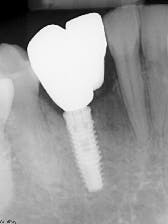

A full-thickness flap is reflected to visualize the bone and confirm positioning through the surgical guide. The guide is designed with windows to visualize proper seating. The surgical guide fully limits the implant drill in all dimensions, including depth, making it possible to drill to the final osteotomy depth and width with one drill. The implant fixture was placed and allowed to heal for four months with a healing abutment. The presurgically planned prosthesis was lab fabricated and delivered (figures 6 and 7).

The patient was pleased with the final result. A CBCT scan allowed this difficult surgical and esthetic case to be planned thoroughly beforehand. 3-D printing economically realized the planning in the actual surgery and prosthesis. 3-D printing in surgical guide fabrication allowed for more efficient and precise implant placement and restoration (figures 8 and 9).